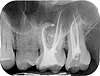

radiographie dents

radiographie des dents